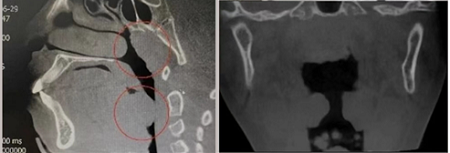

cbct冠状位及矢状位显示腺样体及扁桃体肥大